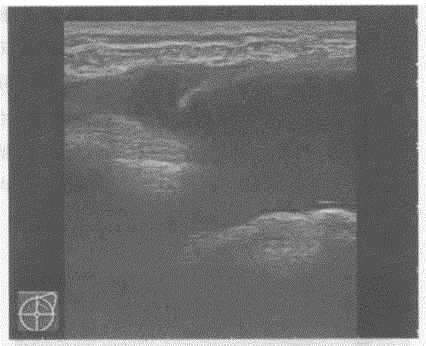

问题 临床资料:女,25岁,隆乳、假体植入术后,自觉双侧乳房大小不对称。 超声综合描述:双侧乳腺可见无回声假体,右侧乳腺内假体形态规则,边界清晰,其周围未见异常回声区;左侧乳腺内假体失常态,外上象限处假体边缘不连续,周边可见不规则无回声区。 超声提示:

选项 A.双侧乳腺假体植入术后假体未见异常 B.双侧乳腺假体植入术后右侧乳腺内假体破裂 C.双侧乳腺假体植入术后左侧乳腺内假体破裂 D.双侧乳腺假体植入术后左侧乳腺内假体移位

答案 C